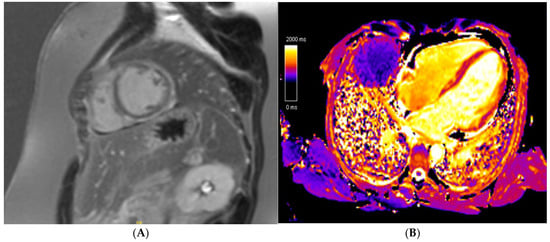

Non-ischaemic replacement fibrosis or fatty replacement in the presence or absence of LV dysfunction (LV EF < 50%) or regional wall motion abnormalities constitute the main imaging findings required for an NDLVC diagnosis. Cine imaging, T1 mapping, and LGE imaging should be performed if there is suspicion of NDLVC. The presence of LGE in NDLVC is why cardiac MRI is key when evaluating athletes with NDLVC. Similar to DCM, an inflammatory (acute or chronic myocarditis) or genetic component (DSP, FLNC, Desmin [DES], Phospholamban [PLN], LMNA) are the main drivers towards myocardial fibrosis in NDLVC [75]. The extent and degree of scarring again offers substantial prognostic information, similar to the DCM phenotype (Figure 6).

Figure 6. A 21 year old endurance athlete, referred for screening as her mother was diagnosed with arrhythmogenic cardiomyopathy secondary to a Desmoplakin pathogenic variant. The athlete was also gene-positive, with a normal ECG and echocardiogram. Cardiac MRI identified a ring-like subepicardial scar on post-contrast imaging (A), with a diffusely elevated T1 (B), resulting in a diagnosis of non-dilated left ventricular cardiomyopathy.

The NDLVC may also act as a precursor to DCM. The presence of non-ischaemic fibrosis predating LV dilatation and/or dysfunction is well established [85]. Unexplained ventricular arrhythmias may also be the manifestation of early concealed cardiomyopathy [86], hence why cardiac MRI to rule out scarring is pivotal in these patients.